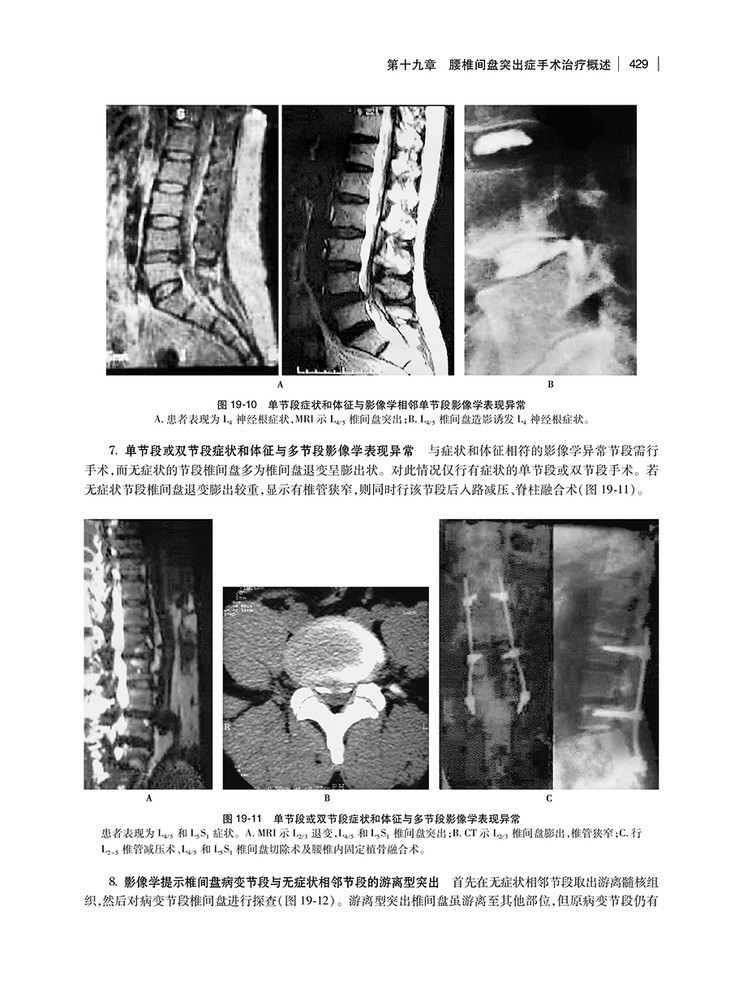

第十九章 腰椎间盘突出症手术治疗概述